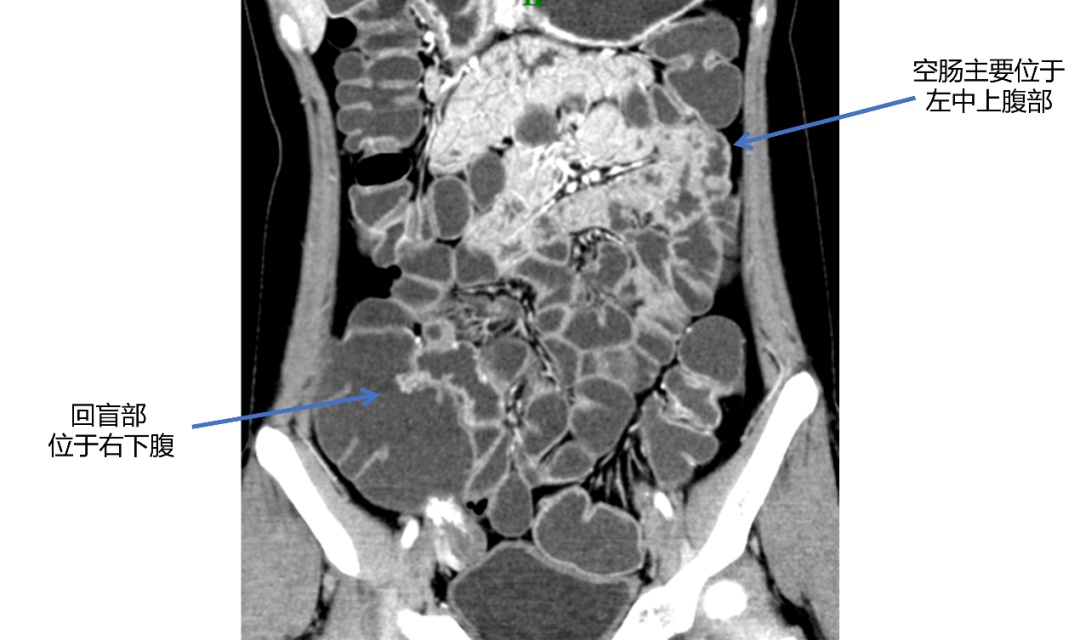

经过仔细的研读,放射科赵雪松医生发现了端倪——原来,刘女士存在先天性的小肠旋转不良问题,依靠常规的经验来读片可能会“误入歧途”!

“正常人的空肠主要位于左中上腹(如图1),回盲部位于右下腹,而她的空肠在右上腹,回盲部范围位于左下腹的位置,因此定位及定性诊断应为回盲部的一个炎性肉芽肿(如图2蓝色箭头处)”赵雪松医生分析道。

在放射科“火眼金睛”的探查下,胃肠外科张弢医生结合患者病史和病变位置,做出了手术的决定。几天后的手术中,果然发现了她回盲部的炎性肉芽肿,及时进行了手术,避免了错误的手术定位以及其继续生长可能造成的肠梗阻等问题。术后一周不到,刘女士便顺利出院了,回归正常饮食状态的她感到无比庆幸,她笑着说“还是瑞金医院的平台强大!在多学科的合作努力下,成功帮我找到了隐藏多年的病因……”

据放射科主任严福华教授介绍,先天性小肠旋转不良是一种先天性肠道畸形,常常发生在胚胎期肠发育的过程中,很容易发生误诊、漏诊的情况,因此在读片时要仔细观察肠管的位置,否则容易做出错误的解剖学定位。